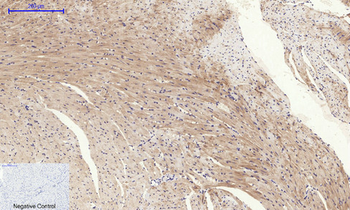

Immunohistochemical analysis of paraffin embedded Human brain tissue labeling Tau with orb1294394 at 1/200.